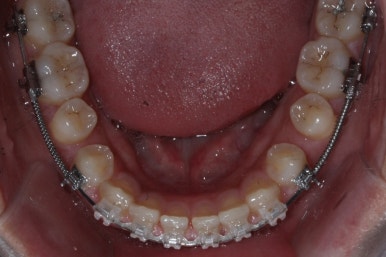

전반적으로 흩어져 있던 틈새를 특정 위치로 모으기 시작합니다.

앞니 사이의 틈을 제일 보기 싫어하실 것 같으므로 앞니 부터 빠르게 틈을 보아줍니다. 대신 작은 어금니 부위로 틈을 모으는 작업을 하게 됩니다.

점점 앞니 사이의 틈이 없어지는 것을 볼 수 있습니다.

앞니 사이의 없어진 틈은 대신 작은 억므니 부위로 모여져 갑니다.

앞니 사이의 틈이 이제 다 모아졌습니다.